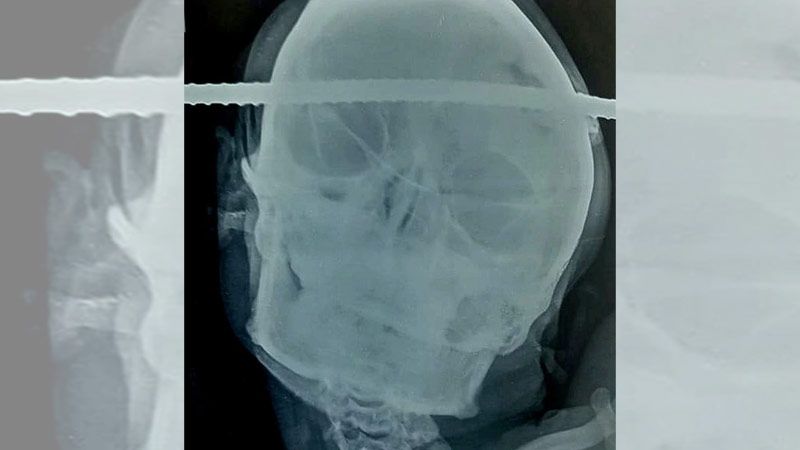

Imágenes sensibles. Sanjay Bahe, un obrero de 21 años, sobrevivió luego de que una barra de hierro le atravesara el cráneo.

Las imágenes de Bahe tendido en la cama antes de la cirugía dieron la vuelta al mundo. Las fotos muestran la barra de hierro que atraviesa la región temporal derecha de su cerebro hasta la región frontal izquierda.